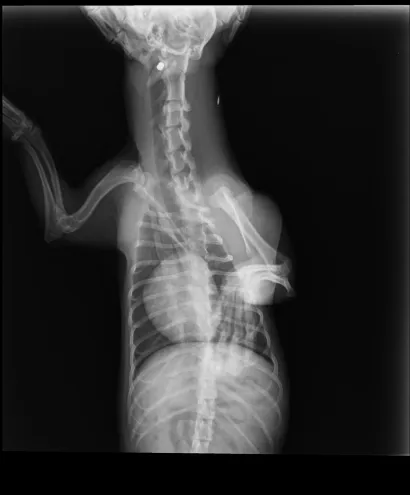

Maleni pas mješanac pogođen je dijabolom u vrat, a budući da je metak ostao smješten na nezgodnom mjestu blizu kralježnice, veterinar Mate Karaula iz Daruvara koji liječi Lenu, odustao je od vađenja metka zbog daljnjeg rizika po kujicu.

Prema nalazu veterinara dr. Mate Karaule, rendgenska snimka pokazala je da se metak, točnije dijabola, nalazi u području između atlasa i aksisa – dijela vratne kralježnice.

- Veličina projektila procijenjena je na 6,10 do 5,16 milimetara, a zbog dubine položaja i blizine kralježnice procijenjeno je da bi pokušaj vađenja mogao izazvati ozbiljne komplikacije. Zbog toga se odustalo od kirurškog vađenja metka.

Pas je primio injekcijsku sedaciju, obavljene su dvije rendgenske snimke i kirurška obrada rane, kazao nam je dr. Karaula.